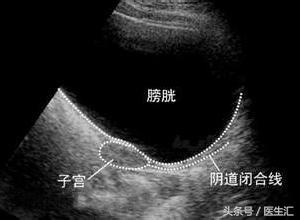

患者因为雌激素很低,子宫没有发育,B超不能准确判断是否为始基子宫。

始基子宫与幼稚子宫的区别:

始基子宫为双侧副中肾管融合后不长即停止发育,子宫极小,多数无宫腔或为实体肌性子宫,无子宫内膜,没有功能,再补充雌激素也长不大;幼稚子宫为双侧副中肾管融合形成子宫后发育停止所致,有子宫内膜。

子宫和人是一样的,人要靠吃饭长大,子宫要靠吃雌激素长大,患者为低雌激素性闭经,雌激素非常低,第二性征没有发育,B超子宫偏小,可能为幼稚子宫,是因为缺乏雌激素导致的,而低促性腺激素性闭经患者同时伴有子宫异常比较少见。

当补充雌激素后,患者第二性征发育,子宫也逐渐长大,当补充孕激素时,能撤退出血,表明这个子宫是有功能的,在当时未补充雌激素时为幼稚子宫;如果当补充雌激素后,患者第二性征发育,但子宫仍未长大,则为无功能的子宫,才称为始基子宫。